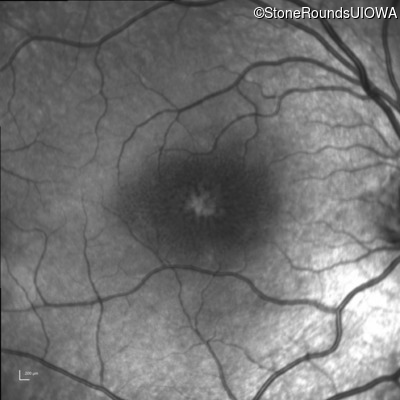

Infrared Fundus Photograph - Right - 20/50

Exemplar